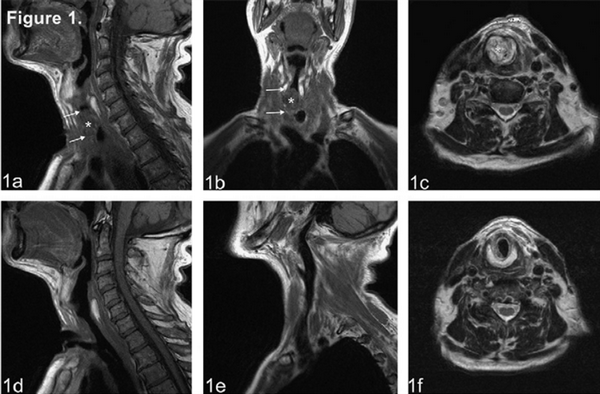

Пациенту было проведено инструментальное обследование: КТ шеи и УЗИ мягких тканей шеи.

При проведении КТ шеи с контрастным усилением. Контраст: Омнискан 0, 5 ммоль/мл 20 мл

КТ - признаки правостороннего паратонзиллярного абсцесса. Признаки выраженной двухсторонней лимфаденопатии.

(Слева) При КТ с КУ в коронарной проекции определяется диффузное двустороннее увеличение небных миндалин, имеются участки неоднородной плотности, свидетельствующие об отеке. Явного абсцесса нет.

(Справа) При МРТ Т1 FS с КУ в аксиальной проекции определяется двустороннее увеличение небных миндалин с интенсивным накоплением контрастного вещества. Небольшие внутренние очаги пониженной интенсивности говорят о наличии подслизистого отека/экссудата.